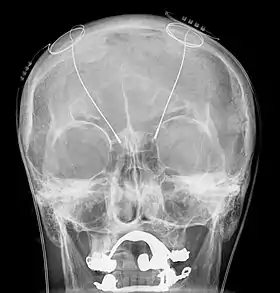

A working diagnosis is made from a neurological examination and evaluation. Parts of a complete examination include a physical examination, magnetic resonance imaging (MRI), patient history, and electrophysiological and accelerometric studies. A diagnosis of solely intention tremor can only be made if the tremor is of low frequency (below 5 Hz) and without the presence of any resting tremors.[1] Electrophysiological studies can be useful in determining frequency of the tremor, and accelerometric studies quantify tremor amplitude. MRI is used to locate damage to and degradation of the cerebellum that may be causing the intention tremor. Focal lesions such as neoplasms, tumors, hemorrhages, demyelination, or other damage may be causing dysfunction of the cerebellum and correspondingly the intention tremor.[14]

Deep brain stimulation treats intention tremors, but does not help related diseases or disorders such as dyssynergia and dysmetria.[17] Deep brain stimulation involves the implantation of a device called a neurostimulator, sometimes called a "brain pacemaker". It sends electrical impulses to specific parts of the brain, changing brain activity in a controlled manner. In the case of an intention tremor, the thalamic nuclear region is targeted for treatment. This form of treatment causes reversible changes and does not cause any permanent lesions. Since it is reversible, deep brain stimulation is considered fairly safe. Reduction in tremor amplitude is almost guaranteed and sometimes resolved. Some individuals have seen sustained benefits in MS progression.[18]